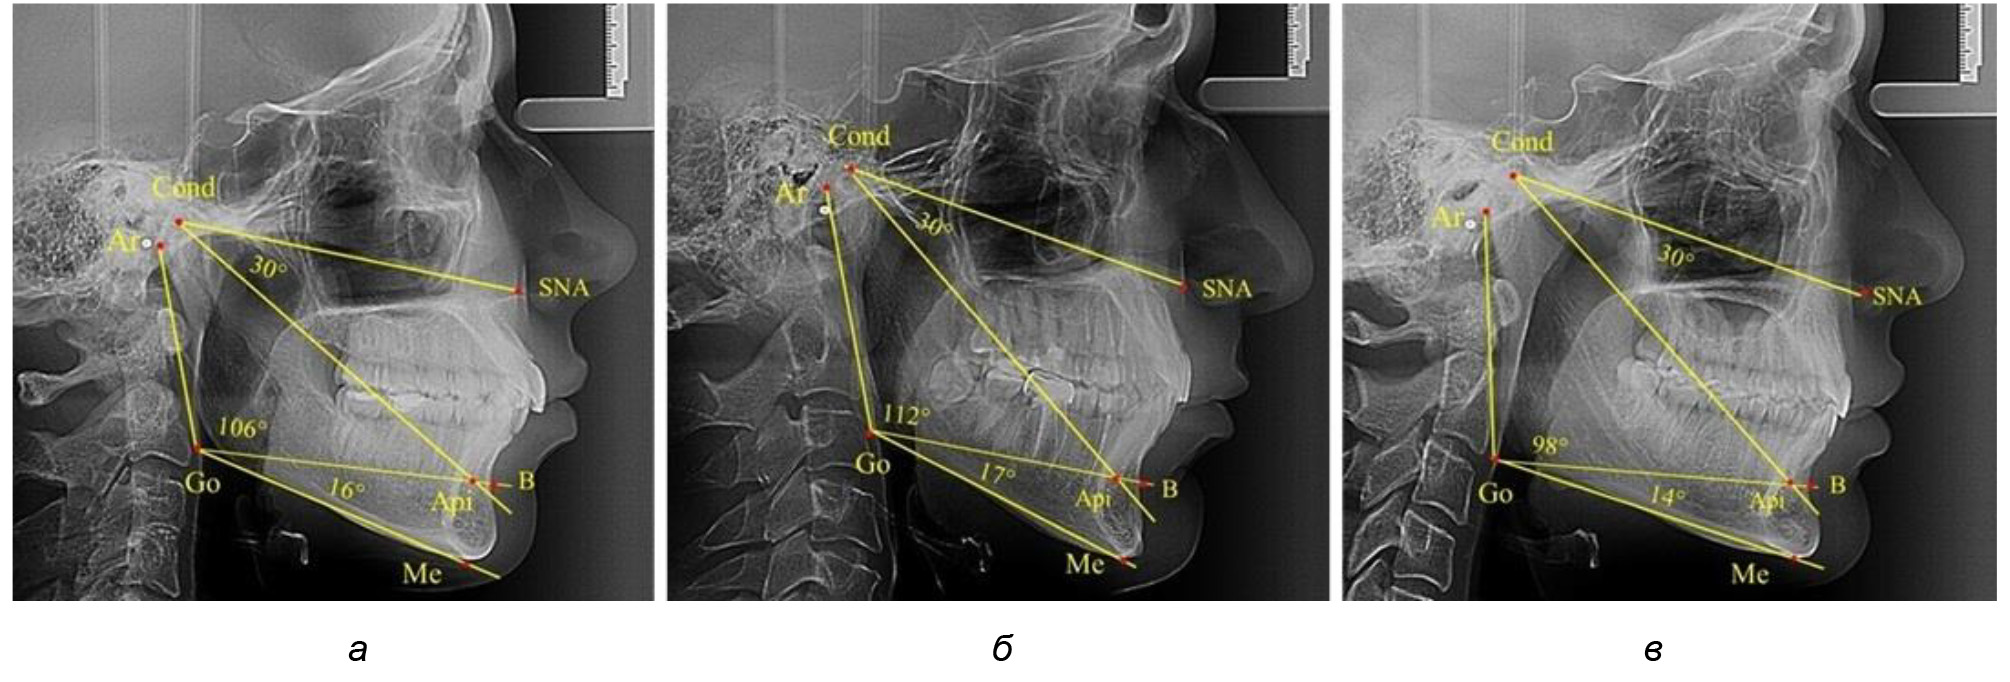

В то же время нижнечелюстной угол варьировал в широких пределах, в частности от 112 до 127°, и его средние значения при физиологическом прикусе составляли (120,57 ± 1,43)°. При этом составляющие части нижнечелюстного угла имели различия. Так, показатель угла Ar-Go-Api варьировал от 110 до 117°, при средних значениях – (107,12 ± 1,73)°. Величина угла Api-Go-Me составляла в среднем (13,56 ± 1,09)° при минимальных значениях 6° и максимальном показатели 19°. Анализируя параметры нижнечелюстного угла на телерентгенограммах с различными типами нижнечелюстного угла, выявлено, что у людей с нейтральными типами угла (в пределах от 119 до 123°) средний показатель был (121,83 ± 0,62)°. Величина угла Ar-Go-Api составила (107,89 ± 1,62)°, а угол Api-Go-Me был (13,83 ± 1,12)°.

При вертикальном типе нижнечелюстного угла его средние значения составили (125,51 ± 0,44)°, и достоверно отличалась от показателей людей с нейтральными значениями нижнечелюстного угла. Величина угла Ar-Go-Api составила (115,49 ± 2,14)°, а угол Api-Go-Me был (13,97 ± 1,26)°.

Для горизонтального типа роста было характерно достоверное р ˂ 0,05 уменьшение нижнечелюстного угла до (115,57 ± 0,56)°. Величина угла Ar-Go-Api составила (102,71 ± 1,62)°, а угол Api-Go-Me был (12,86 ± 0,74)° (рис. 3).

Рис. 3. Особенности ТРГ при нейтральном (а), вертикальном (б) и горизонтальном (в) типе угла нижней челюсти в постоянном прикусе